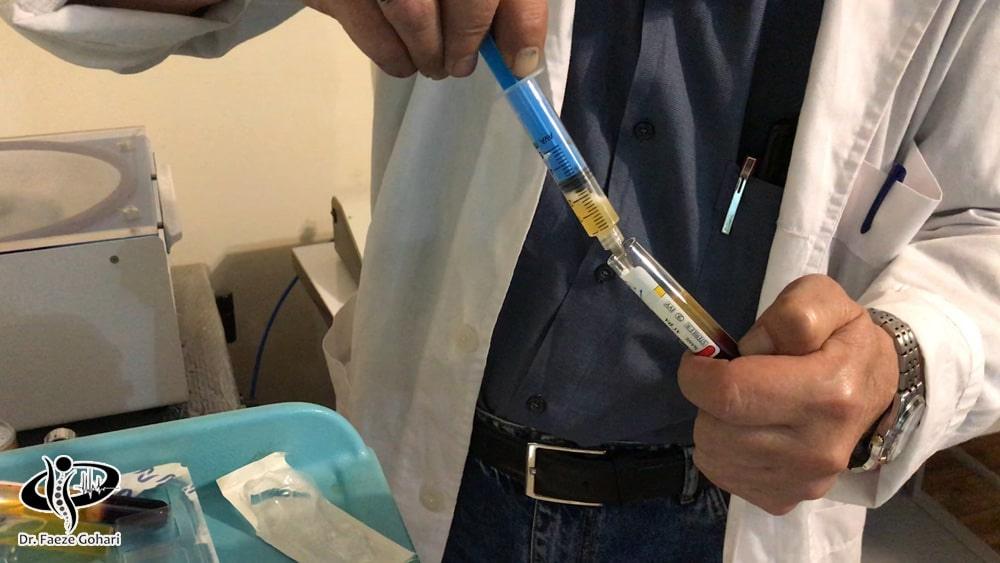

در درمان با سلولهای بنیادی، پیآرپی (پلاسمای غنی از پلاکت) و سلولهای بنیادی به طور مشترک و بهصورت یک کوکتل تزریقی استفاده میشوند. پیآرپی با تحریک و تسریع روند بازسازی سلولهای بنیادی، نقش مؤثری در کاهش التهاب دارد و به تسریع بهبود بافتها کمک میکند. علاوه بر این، پیآرپی میتواند درد ناشی از تزریق را کاهش دهد و فرایند درمان را راحتتر کند. فرایند تزریق شامل مراحل زیر است.

تهیه سلولهای بنیادی از بانک سلولی معتبر

معمولاً سلولهای بنیادی بهصورت ویالهای آماده از بانکهای سلولی معتبر تهیه میشوند، چرا که این روش امکان دسترسی به حجم بیشتری از سلولهای بنیادی باکیفیت بالا را فراهم میآورد.

تهیه پی آر پی از خون بیمار

برای تهیه پیآرپی، بیمار باید حدود دو ساعت قبل از زمان تزریق در مطب حاضر شود. در یک محیط استریل، پلاسمای غنی از پلاکت از طریق مراحل زیر استخراج میشود.

تهیه پیآرپی غنی از پلاکت

در این مرحله، پلاسمای غنی از پلاکت (PRP) که اکنون دارای غلظت بیشتری از پلاکتها است، از لایههای دیگر جدا میشود. این پیآرپی آماده استفاده است و میتواند به ناحیه آسیبدیده تزریق شود.

تزریق با هدایت سونوگرافی

پس از آمادهسازی کوکتل تزریقی، سلولهای بنیادی و پیآرپی بادقت و تحت هدایت سونوگرافی در ناحیه لگن تزریق میشوند. بسته بهشدت آسیب، ممکن است تعداد جلسات درمانی به ۳ جلسه افزایش یابد، و فاصله بین تزریقات و تعداد جلسات به تشخیص و نظر پزشک معالج بستگی دارد.